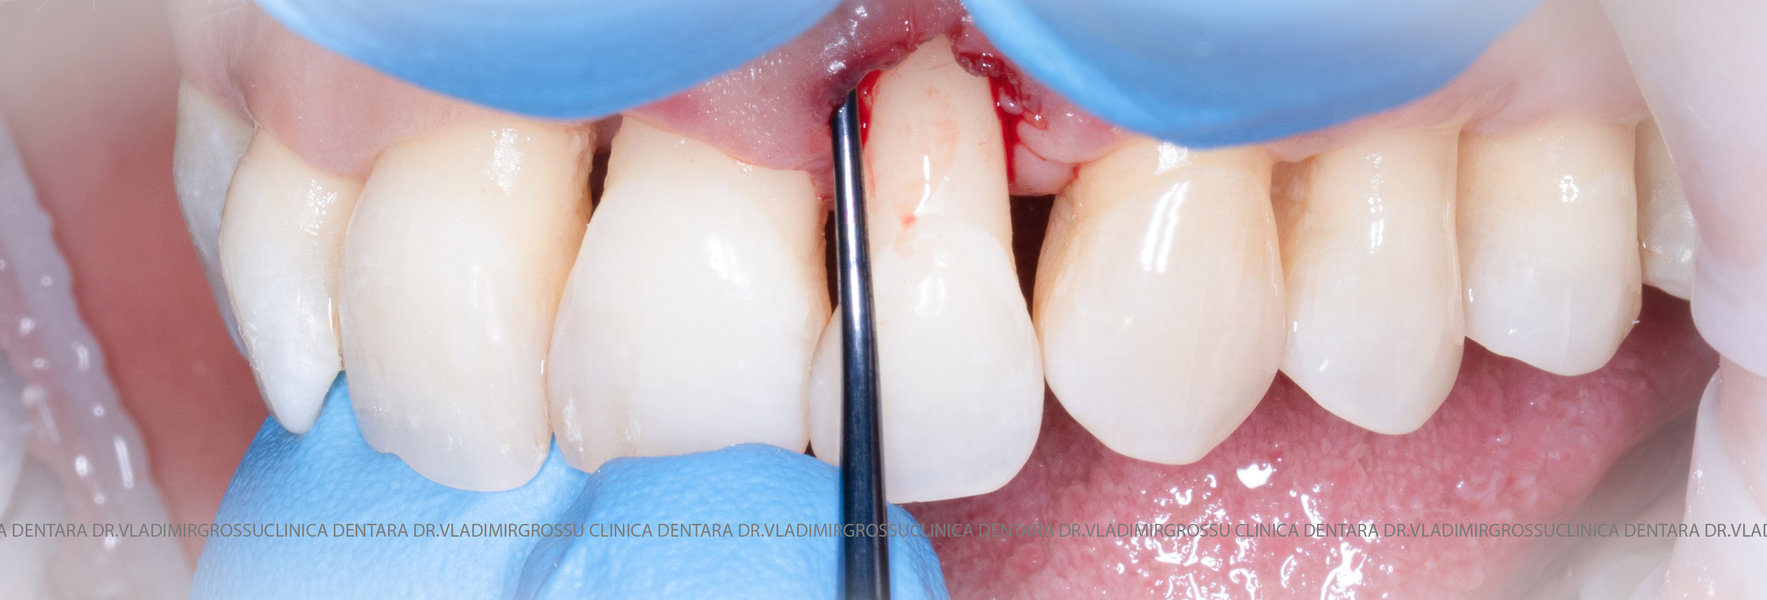

Aditia gingivală este o procedură chirurgicală ce corectează diverse probleme estetice și funcționale, cum ar fi recesiunea gingivală. În implantologia modernă, aditia de țesut moale este utilizată aproape în fiecare intervenție de inserție a implantului dentar pentru a asigura un aspect estetic natural și o bună integrare a implantului în cavitatea bucală.

Adiția osoasă are un rol crucial pentru poziționarea corectă și stabilă a implanturilor dentare. Clinica stomatologică Dr. Grossu din Chișinău promovează o abordare chirurgicală estetică și predictibilă, adaptată fiecărui caz în parte.